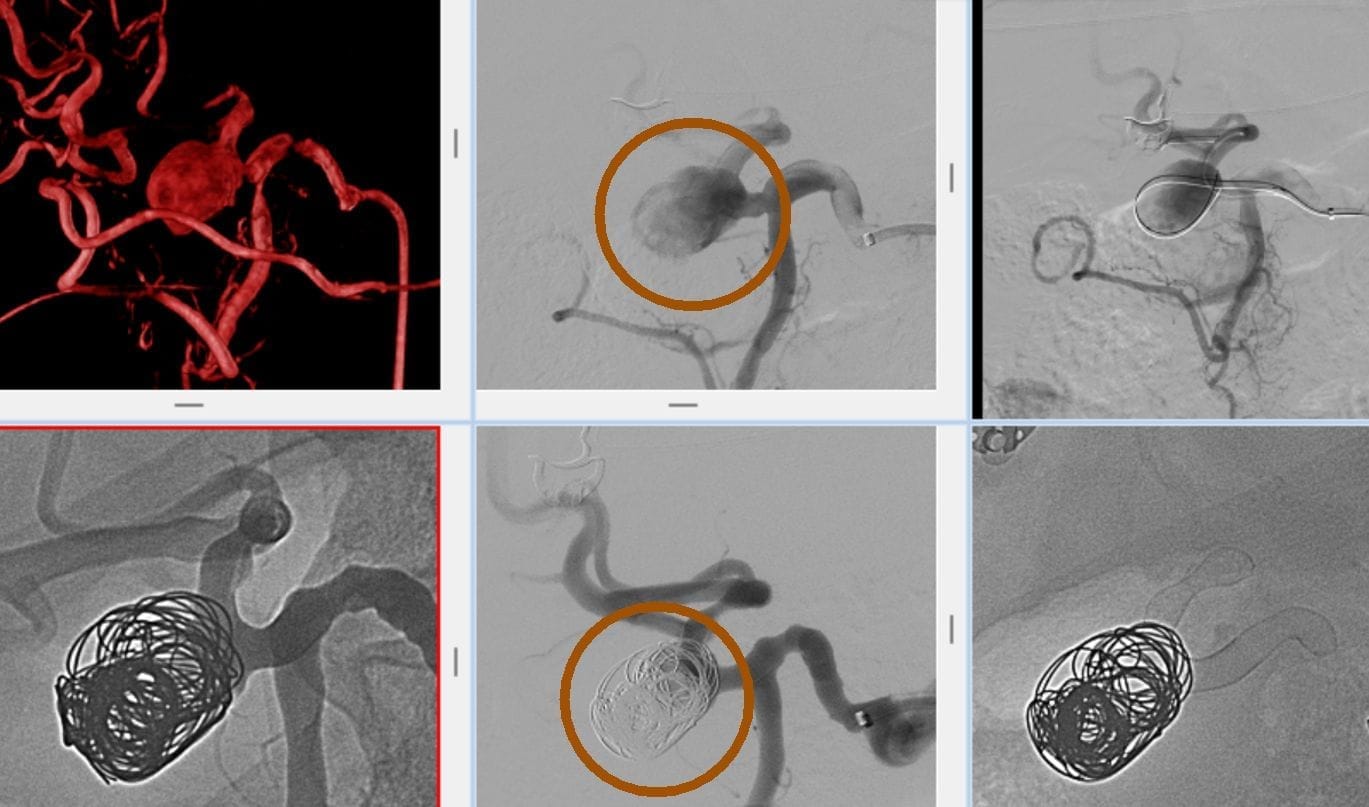

Die Methode findet insbesondere bei blutungsbedingten Erkrankungen Anwendung. Blutungen und Tumore in verschiedenen Organen des Körpers können durch Embolisation kontrolliert werden. Zu den schwerwiegenden Beschwerden, die Patienten erleben, gehören auch lebensbedrohliche Zustände wie zerebrale Aneurysmen und arteriovenöse Malformationen.

- Zerebrale Aneurysmen

Welche Techniken werden bei der Embolisation angewendet?

- Metall-Coils: Kleine Geräte, die aus rostfreiem Stahl oder Platin hergestellt sind und eine präzise Platzierung ermöglichen.

Fallbeispiele